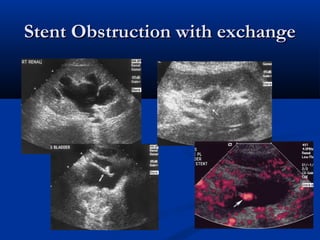

Stent Obstruction with exchange

• #25 Left: increaed hydro with no doppler flow Right: decrease hydro with flow after stent exchange